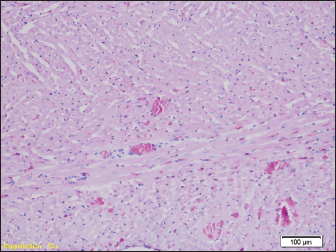

In the liver samples of all groups of rats, relatively uniform changes are observed, which in each sample include a certain degree of congestion, with overcrowding of the centrolobular veins, but also the veins of the portal spaces, as well as the dilation of the sinusoids filled with erythrocytes, while the hepatocytes in places show signs of fluffy degeneration (Figs. 5 and 6.)

Fig. 6. Congested portal blood vessels as well as sinusoids, and hepatocytes with balloon appearance in places (HE, ×200).

Signs of degenerative changes caused by drowning were found in the liver samples. It is believed that drowning and hypotension during recovery lead to irreversible changes in the organs caused by a lack of oxygen. Similar changes were found in other studies, where the liver showed small but numerous clusters of hyaline bodies in the liver sinusoids (Ikeda et al., 1998).

Our results show signs of overcrowding of hepatic sinusoids with partially ballooned hepatocytes. These results were found in previous studies, where hepatocytes had hydropic degeneration (Ibrahim et al., 2022). The changes that can occur to the organs can largely depend on the type of water in which the drowning occurred, from salt water to fresh water. In our study, rats were drowned in water from the Bosnia River. Upon examination of the heart muscle, we found congested blood vessels, with no signs of degeneration. In contrast to our results, Mahrous et al., found signs of cardiac muscle cell damage after drowning in salt water, which were presented as a greater number of vacuoles in the cytoplasm, a reduced number of nuclei in the cells, and an inflammatory infiltrate, but also edema and congestion of blood vessels as in our results (Ibrahim et al., 2022). Christe et al. (2008) found an enlarged heart on the post-autopsy material, with an increased volume of the right atrium and right ventricle, while the left side of the heart was enlarged in only one person (Christe et al., 2008).

However, studies have shown that there are statistical differences in the number of diatoms in false positive cases and actual drowning cases. Therefore, a comprehensive analysis of multiple organs, rather than just one organ, would be more useful for the diagnosis of drowning. Relatively uniform changes are observed in the liver samples of all groups of rats, which in each sample include a certain degree of congestion, with overcrowding of the centrolobular veins, but also the veins of the portal space, as well as dilation of sinusoids-filled with erythrocytes, while hepatocytes in places show signs of paper degeneration.